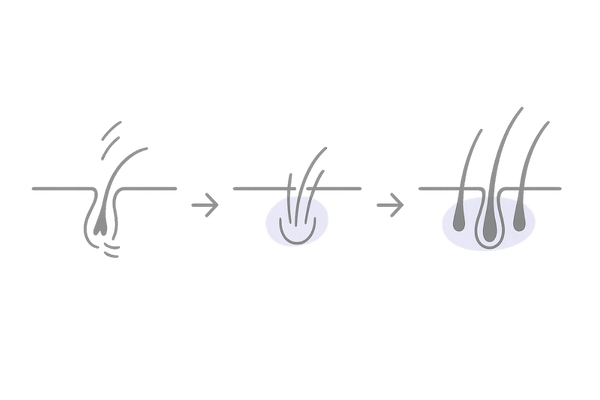

ミノキシジルがヘアサイクルに与える影響

髪の毛には「成長期」「退行期」「休止期」という一連の周期、いわゆる「ヘアサイクル」があります。

薄毛は、このヘアサイクルのうち「成長期」が短くなり、髪が太く長く成長する前に抜け落ちてしまうために進行します。

ミノキシジルは休止期にある毛包に働きかけ、新たな成長期へと移行するのを促す作用を持ちます。

この働きにより短くなってしまった成長期を正常な長さに戻し、細く弱々しい髪の毛を太く健康な髪へと育て直す手助けをします。

休止期の毛包を成長期へ導く

ミノキシジルの最も重要な働きのひとつが、活動を休んでいる毛包(休止期毛包)を刺激し、再び髪を成長させる段階(成長期)へと誘導することです。

薄毛が進行している頭皮では、多くの毛包が休止期のまま留まっています。

ミノキシジルは、これらの眠っている毛包を目覚めさせ、新たな髪の毛を生やす「スイッチ」を押す役割を果たします。

毛母細胞の活性化と血管拡張作用

髪の毛は、毛根の一番奥にある毛母細胞が分裂を繰り返すことで作られます。

ミノキシジルは、この毛母細胞に直接作用し、細胞分裂を活性化させます。同時に、毛根周辺の毛細血管を拡張させて血流を増やす働きも持ちます。

この二つの相乗効果により、髪の成長に必要な酸素や栄養素が毛母細胞へ豊富に届けられ、より強く太い髪の毛が育つ環境を整えるのです。